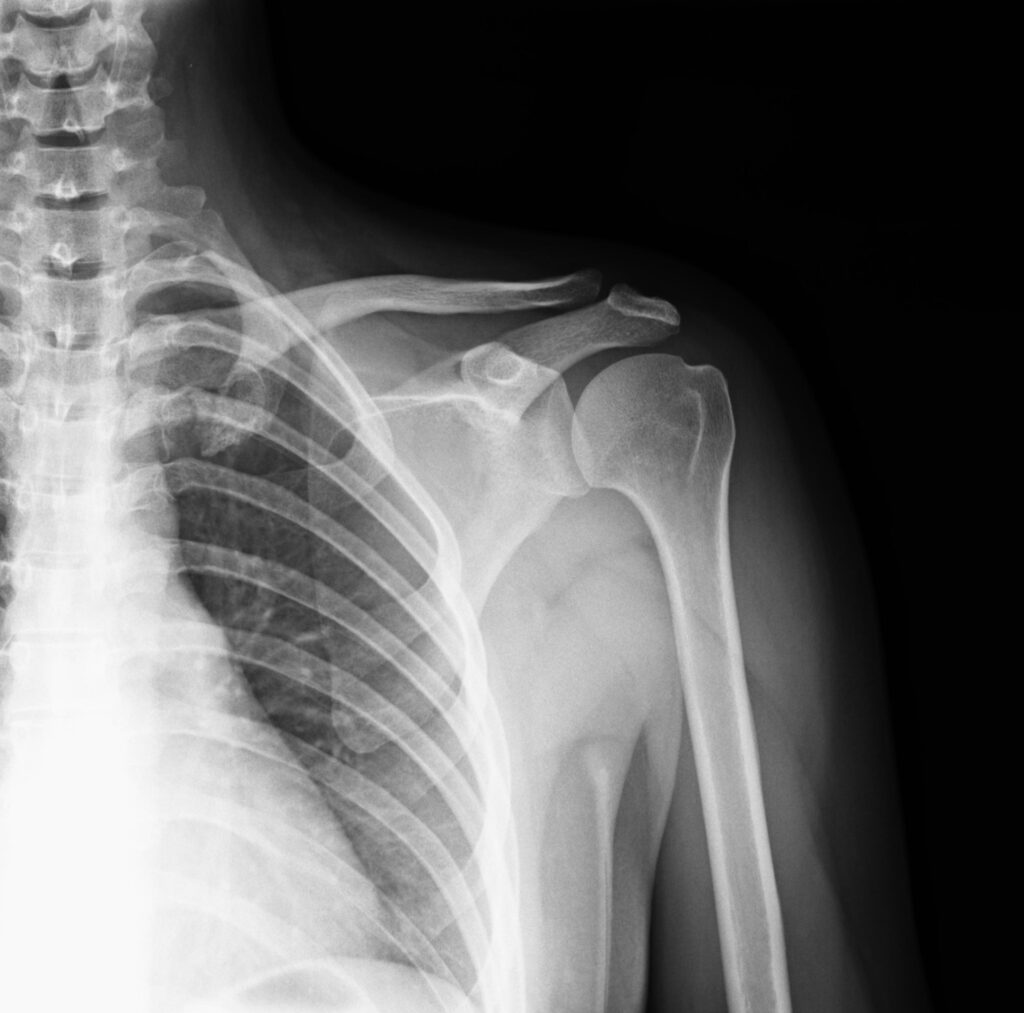

レントゲンを撮ると…「肩にあるはずのない白い影」が。

診断は「石灰沈着性腱板炎」。